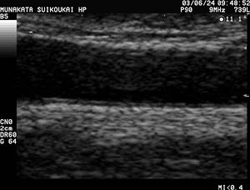

頚動脈エコー例

頚動脈エコー

内頚動脈の内膜厚を

測定しているところ